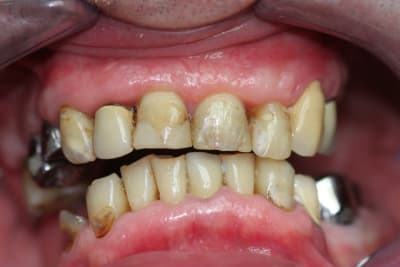

Allez, cas fini cette semaine, je vous le présente tel qu'il est arrivé.

La pano est dégueulasse, à l'époque je n'avais pas encore la mienne, merci les radiologues.

Pour compléter donc:

-pas de lésions apicales visibles, les dents non dévitalisées répondent au test de vitalité.

-Pas de poches supérieures à 6 mm.

-Pas de photo du visage pré-traitement, le patient ne sourie pas, probablement complexé, et je n'ai pas voulu en rajouter.

-Brossage moyen, ok dès la première séance après enseignement de l'hygiène.

-La 23 est foutue, cariée jusqu'au trognon.